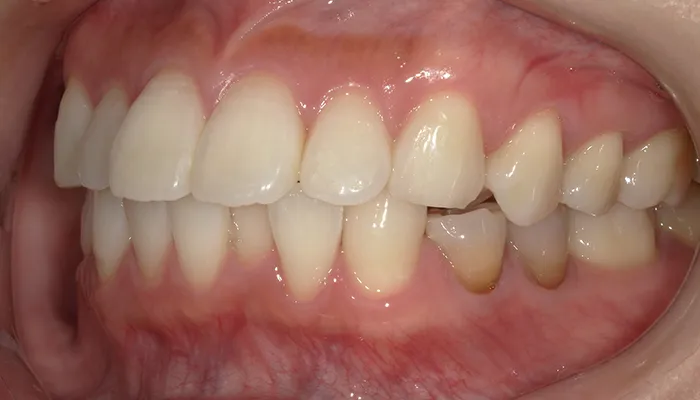

治療前

口腔内写真とレントゲン写真

右下5番は大きく崩壊しており、保存不可能な状態でした。

また、下顎前歯部を中心に叢生があり、歯列が不均一でした。咬合関係が不安定で、清掃性も低下していました。

全体的に歯の色もやや黄みを帯びており、患者様からも審美的な改善希望が強くありました。